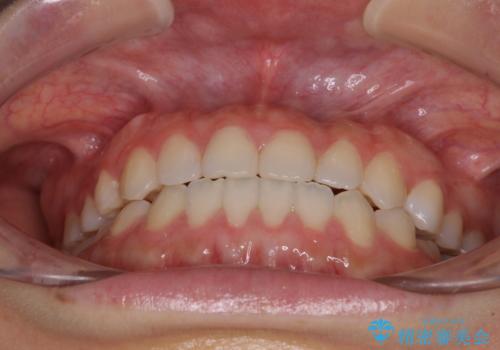

治療期間中は奥歯がほとんど咬めない状態が続き、食事に大変苦労されました。

最終的には隙間もしっかりと閉じ、奥歯も咬みやすい状態でしあげることができました。